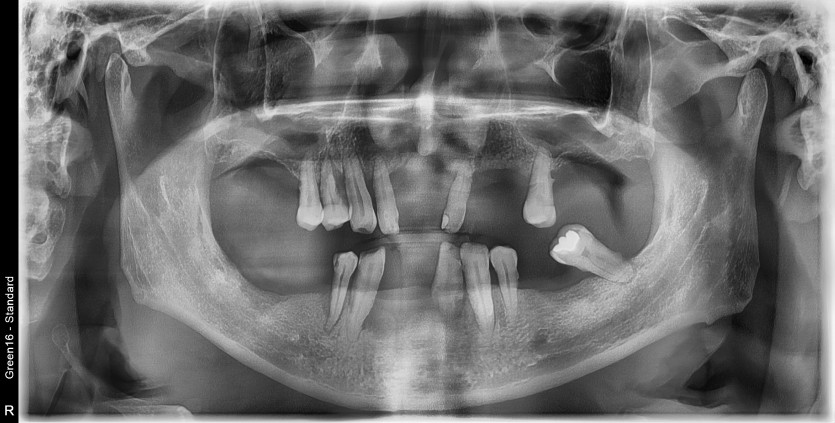

만 50세 전체임플란트 증례입니다.

전체 임플란트 증례입니다.

18개의 임플란트로 완성하였습니다.